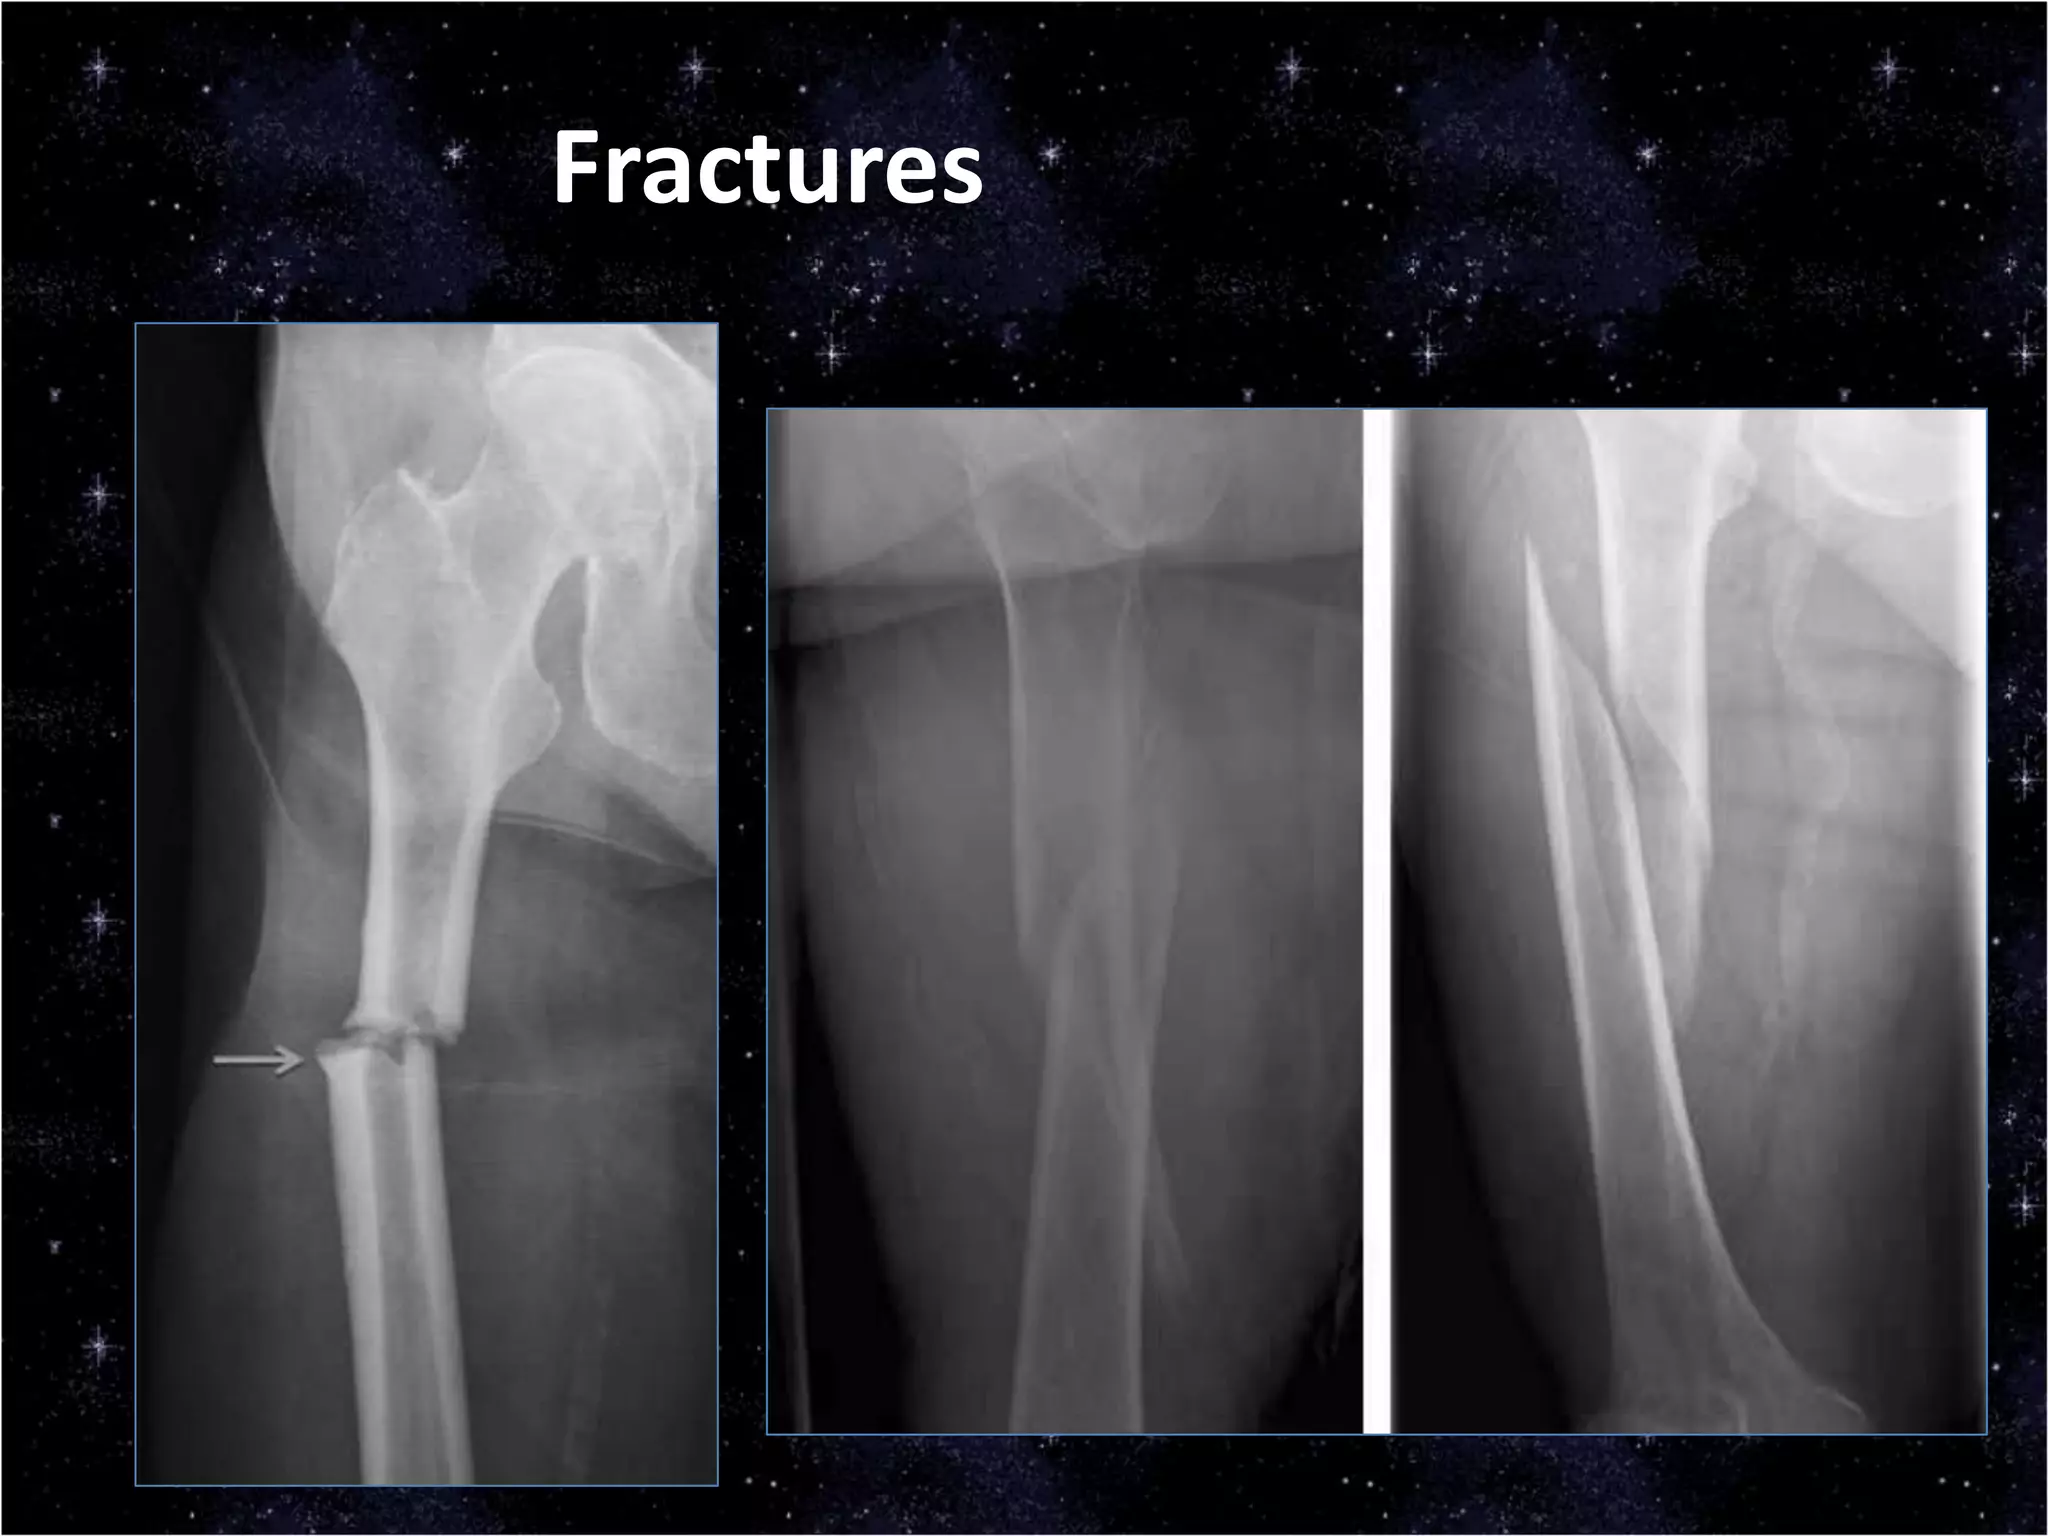

This document discusses trauma to the pelvis, hips, knees, ankles, and feet. It covers anatomy, imaging techniques, and types of fractures and dislocations that can occur in these areas. The types of fractures discussed include pelvic ring fractures, acetabular fractures, and fractures of the femur, tibia, fibula, and bones of the foot. Imaging views used include AP, inlet, and outlet views of the pelvis. Dislocations and fractures of the knee, ankle, and foot joints are also examined.